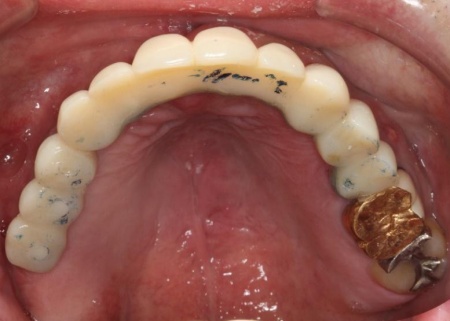

治療後

インプラントが骨にしっかりとなじんだことを確認したら、白くて強度の高い人工歯「ジルコニアクラウン」を装着しました。

また、インプラント治療と並行して、合わなくなっていた被せ物・詰め物・既存のインプラントを作り替えます。

左上奥歯は、装着されていた金属の古い詰め物を外し、白い樹脂を直接詰める「ダイレクトボンディング」で修復しました。